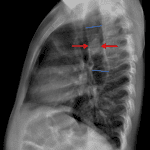

Age: 3

Sex: Female

Indication: Choking, history of esophageal atresia repair

- Patulous, gas-filled esophagus with gradual tapering distally near the gastroesophageal junction. Lobular soft tissue density in the mid esophagus

- No focal airspace opacification, pleural effusion, or pneumothorax

- Borderline enlargement of the cardiothymic silhouette

- Right aortic arch

- Impacted food bolus

- Right aortic arch

Patulous, gas-filled esophagus with gradual tapering distally near the gastroesophageal junction. Lobular soft tissue density in the mid esophagus is concerning for impacted food bolus.

No focal airspace opacification, pleural effusion, or pneumothorax.

Borderline enlargement of the cardiothymic silhouette.

Right aortic arch. Consider cardiology referral if this finding has not been previously evaluated.